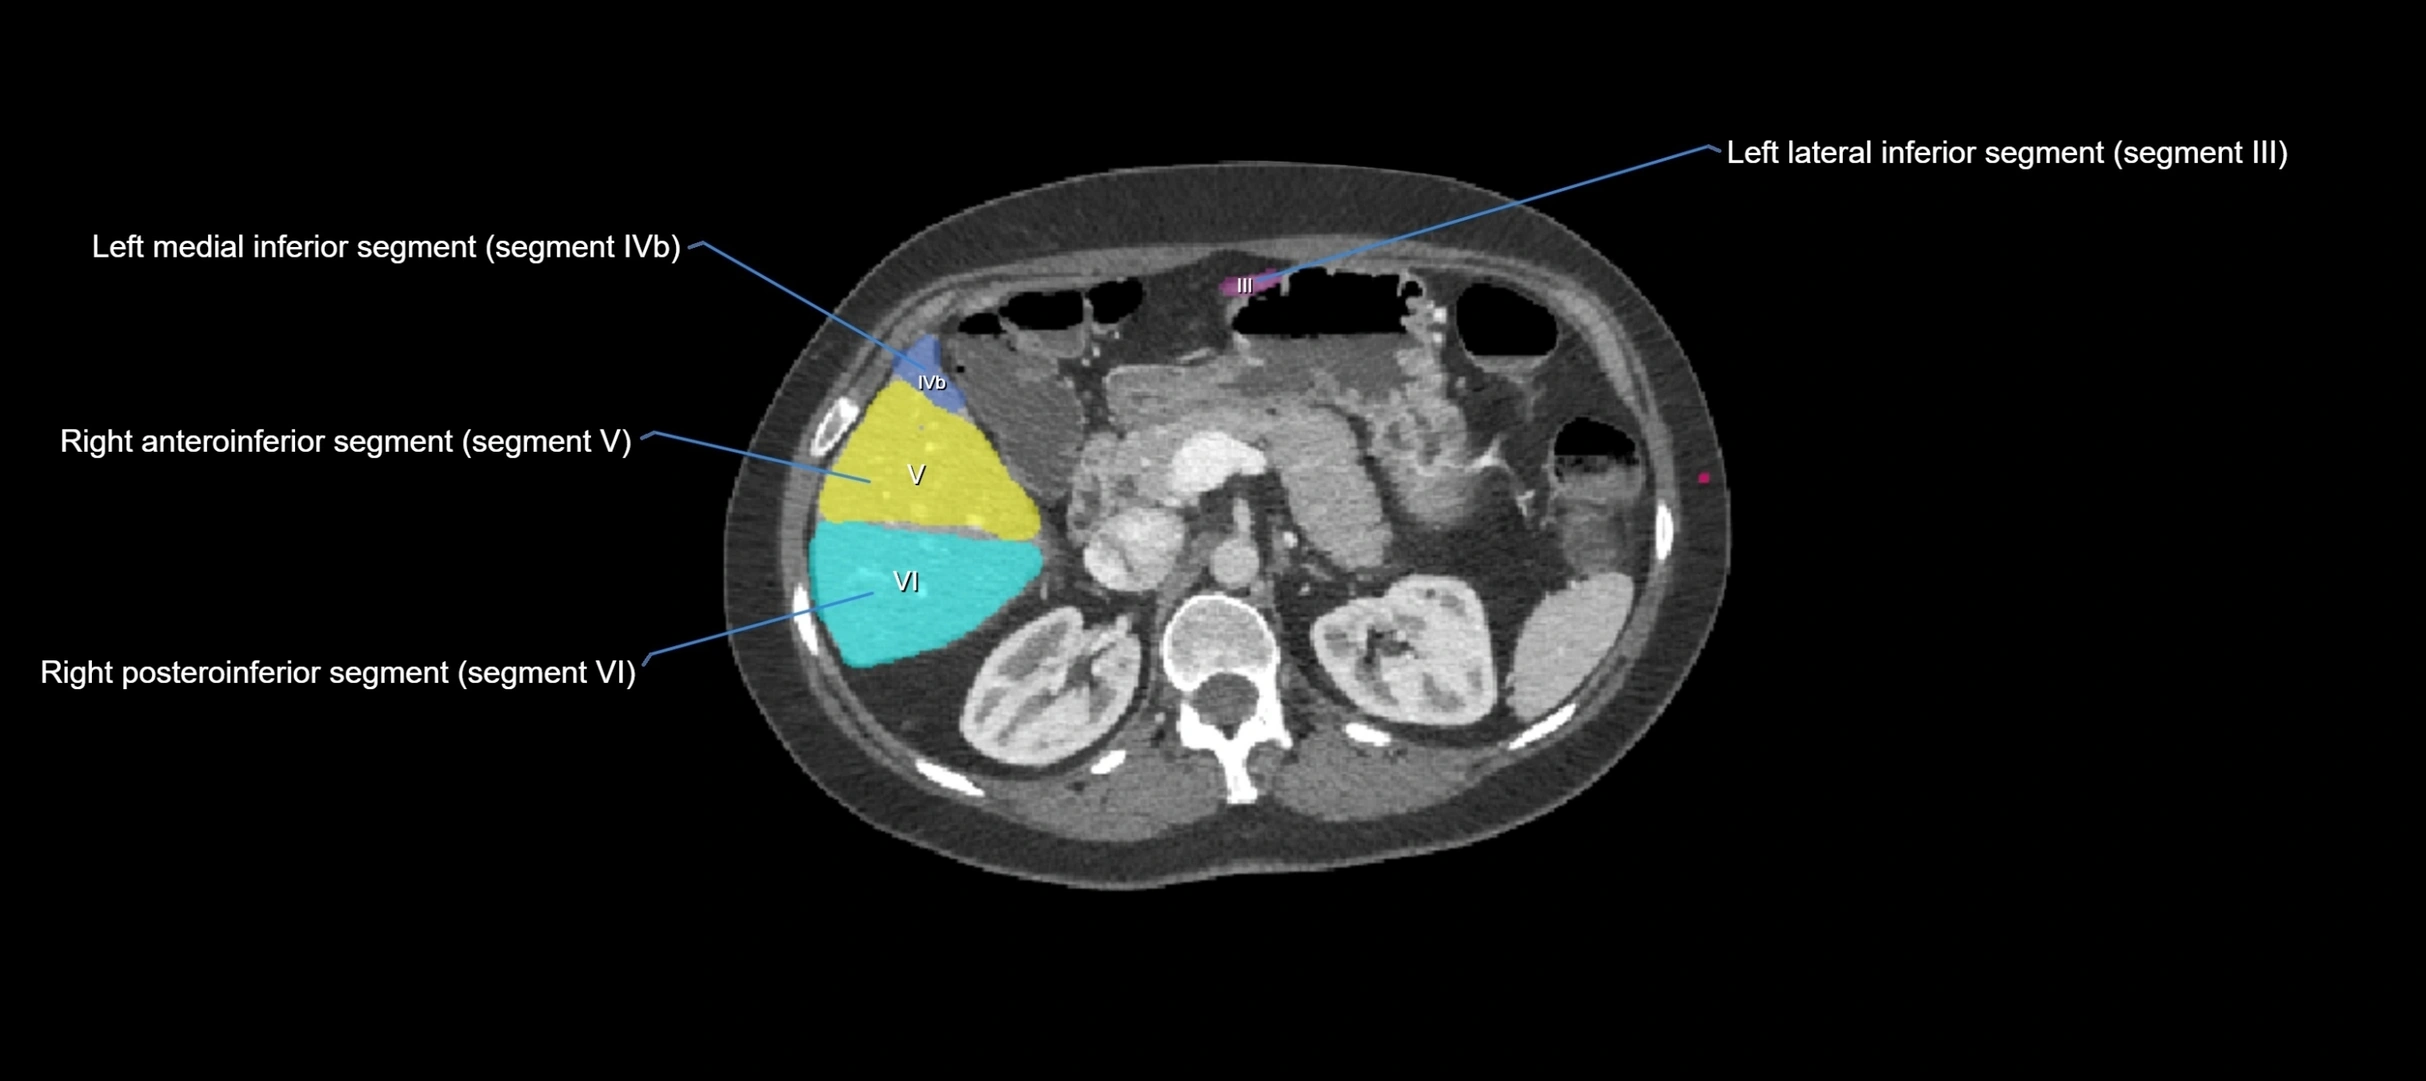

CT Appearance

CT Pre-Contrast:

• Caudate lobe appears as a soft-tissue density, isodense to the rest of the liver

• Enlargement may be appreciated in cirrhosis or Budd–Chiari syndrome

CT Post-Contrast:

• Homogeneous enhancement in the portal venous phase, similar to rest of liver

• Independent venous drainage into the IVC may be visualized

• Lesions follow characteristic CT enhancement patterns (HCC: arterial hyperenhancement with washout; hemangiomas: peripheral nodular enhancement with centripetal fill-in)